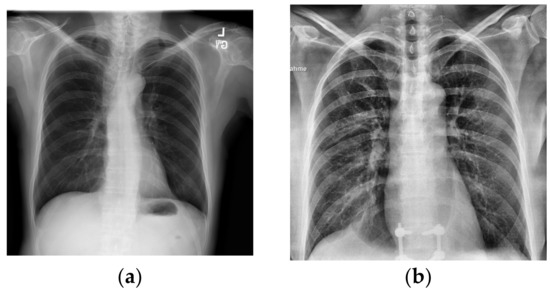

Figure 1.

X-rays of healthy and infected patients. X-rays from [7,8]. (a) Sample X-ray for healthy lungs. (b) Sample X-ray for COVID-19-infected lungs.